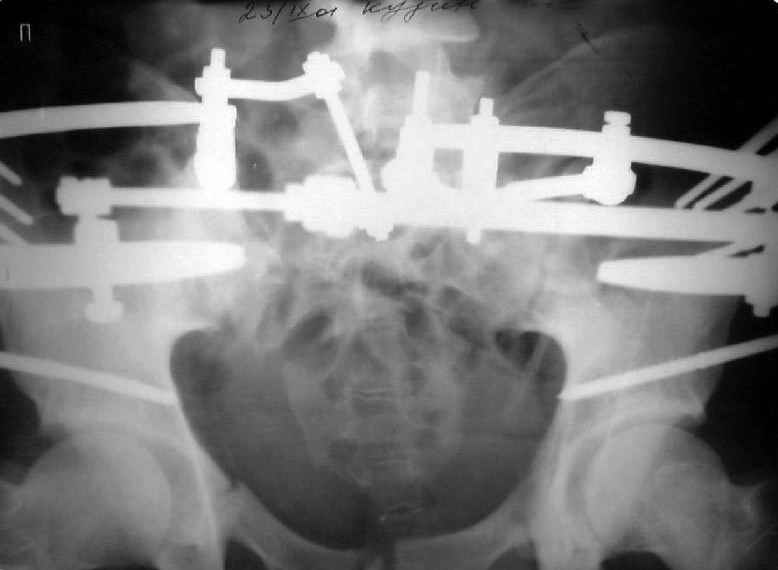

Для информации к размышлению о возможности исправления имеющейся деформации предлагаю похожий случай.